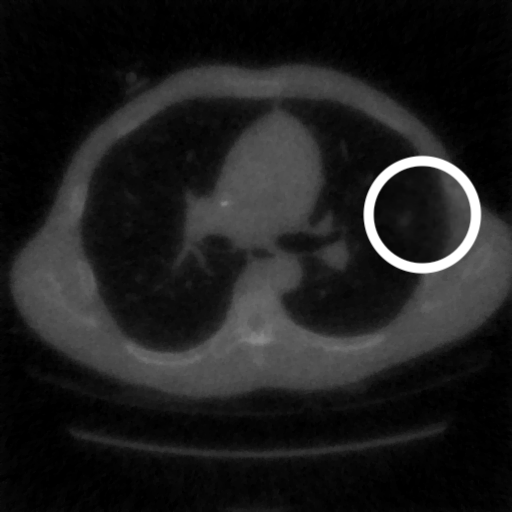

3.1.3 Example 2: data driven reconstruction methods in lung CT screening

There is sufficient evidence that screening for certain tumours using CT images may improve prognosis of cancer survivability (citep \@BBN(Boiselle, 2013)). As mentioned above, in order to gain better image quality with less X-ray dose, many enhanced regularization techniques with integrated machine learning steps have been suggested for CT reconstruction, and in a full reference setting they are commonly evaluated by applying PSNR and SSIM, see e.g. (citep \@BBN(Adler and Öktem, 2018; Hendriksen, Pelt, and Batenburg, 2020; Unal, Ertas, and Yildirim, 2021)). As CT images are generally taken to perform a clinical task, they are not the final step of a medical process but often the initial one. Therefore the definition of what makes a good image heavily depends on the task in hand, and for prognosis related cancer the identification of tumours is of upmost importance.

In on-going research on photon counting detector types and screening procedures for lung cancer (EPSCR grant: EP/W004445/1) an experiment was conducted testing enhanced reconstruction algorithms. Simulations using less than 10% of a clinical X-ray dose were performed to investigate if data-driven methods could sufficiently enhance the images to clearly see the tumours in the lungs while providing very low amount of dosage to the patients. The corresponding data was a CT-dose simulation, using images from the open LIDC-IDRI dataset (citep \@BBN(Armato et al., 2011)) as references, as well as simulated and reconstructed images with in-house software. Figure 3 shows the results of the experiment. We show the reference image used as basis for the simulation, together with five different reconstruction algorithms. The first is an iterative solver, a gradient descend algorithm with TV minimization (citep \@BBN(Sidky et al., 2012)) and (c)-(f) correspond to machine learning methods: FBPConvnet is a denoising algorithm that cleans the bad image (citep \@BBN(Jin et al., 2017)), LPD is an iterative unrolled method that combines traditional solvers with machine learning (citep \@BBN(Adler and Öktem, 2018)), Noise2Inverse is a self-supervised learning method (i.e. does not require ground truth data) (citep \@BBN(Hendriksen et al., 2020)) and ItNet is another iterative unrolled method, the best performing winner of the AAPM DL-Sparse-View CT challenge (citep \@BBN(Genzel, Macdonald, and März, 2021)). ItNet is also judged here as the best result according to PSNR, SSIM and LPIPS.

Refer to caption

(a) Reference

(b) (27.6, 0.70, 0.37)

(c) (31.9, 0.73, 0.29)

(d) (32.5, 0.84, 0.19)

(e) (32.5,0.77, 0.20)

(f) (33.0, 0.89, 0.12)

Figure 3: Reference image (a) and outputs of different reconstruction methods (b)-(f) applied to dose simulated data. PSNR/SSIM/LPIPS are unable to identify the best reconstruction (c), where also the tumour is visualized well.

FR-IQA mismatches

This experiment was performed to evaluate the quality of different kinds of CT reconstruction, and especially the lung tumour detection capabilities thereof. The best result according to the chosen IQA measures is given by ItNet in Figure 3(f), which performs visually poorly. Not only the tumour (zoomed in white circle) is significantly less visible in the reconstruction, but ItNet also produces structures in the lung that are different than the ones in the reference image; it blurs and lengthens much of the soft tissue present in the lungs and it also created structure from noise in some places. Moreover, the image is overly smooth. Comparing the other reconstruction algorithms, it seems that FBPConvnet Figure 3(c) is the one performing best at preserving the shape of the lung nodule, even when the resulting image contains enhanced pixel-level noise.

We can see here that the qualitative findings strongly contradict the numbers provided by the selected measures. The reconstruction of ItNet, Figure 3(f), is outperforming the other reconstructions in regards of the measures, and the qualitative winner FBPConvnet, Figure 3(c), is judged as second worst by the same measures. This experiment suggests that the discussed measures are not a good choice for that kind of CT reconstruction applications and are yielding misleading results.

While pixel-independent random noise may be a worse effect in a natural image than a slightly oversmooth reconstruction, this is not true in CT images, where small structures may disappear if smoothing is promoted against edge preservation. In iterative reconstruction algorithms such choices are explicitly made by choosing the prior appropriately, in data-driven models the researcher has limited control on the type of implicit priors the algorithm learns from the data, i.e. model builders do not know what the algorithms chooses to learn from the ground truth. In these cases appropriate evaluation would therefore be even more important to ensure quality. If this is followed by a blind evaluation using non-appropriate metrics, the promotion of less desirable images can happen, chosen by an implicit assumption on the metric rather than the actual goal of the task.